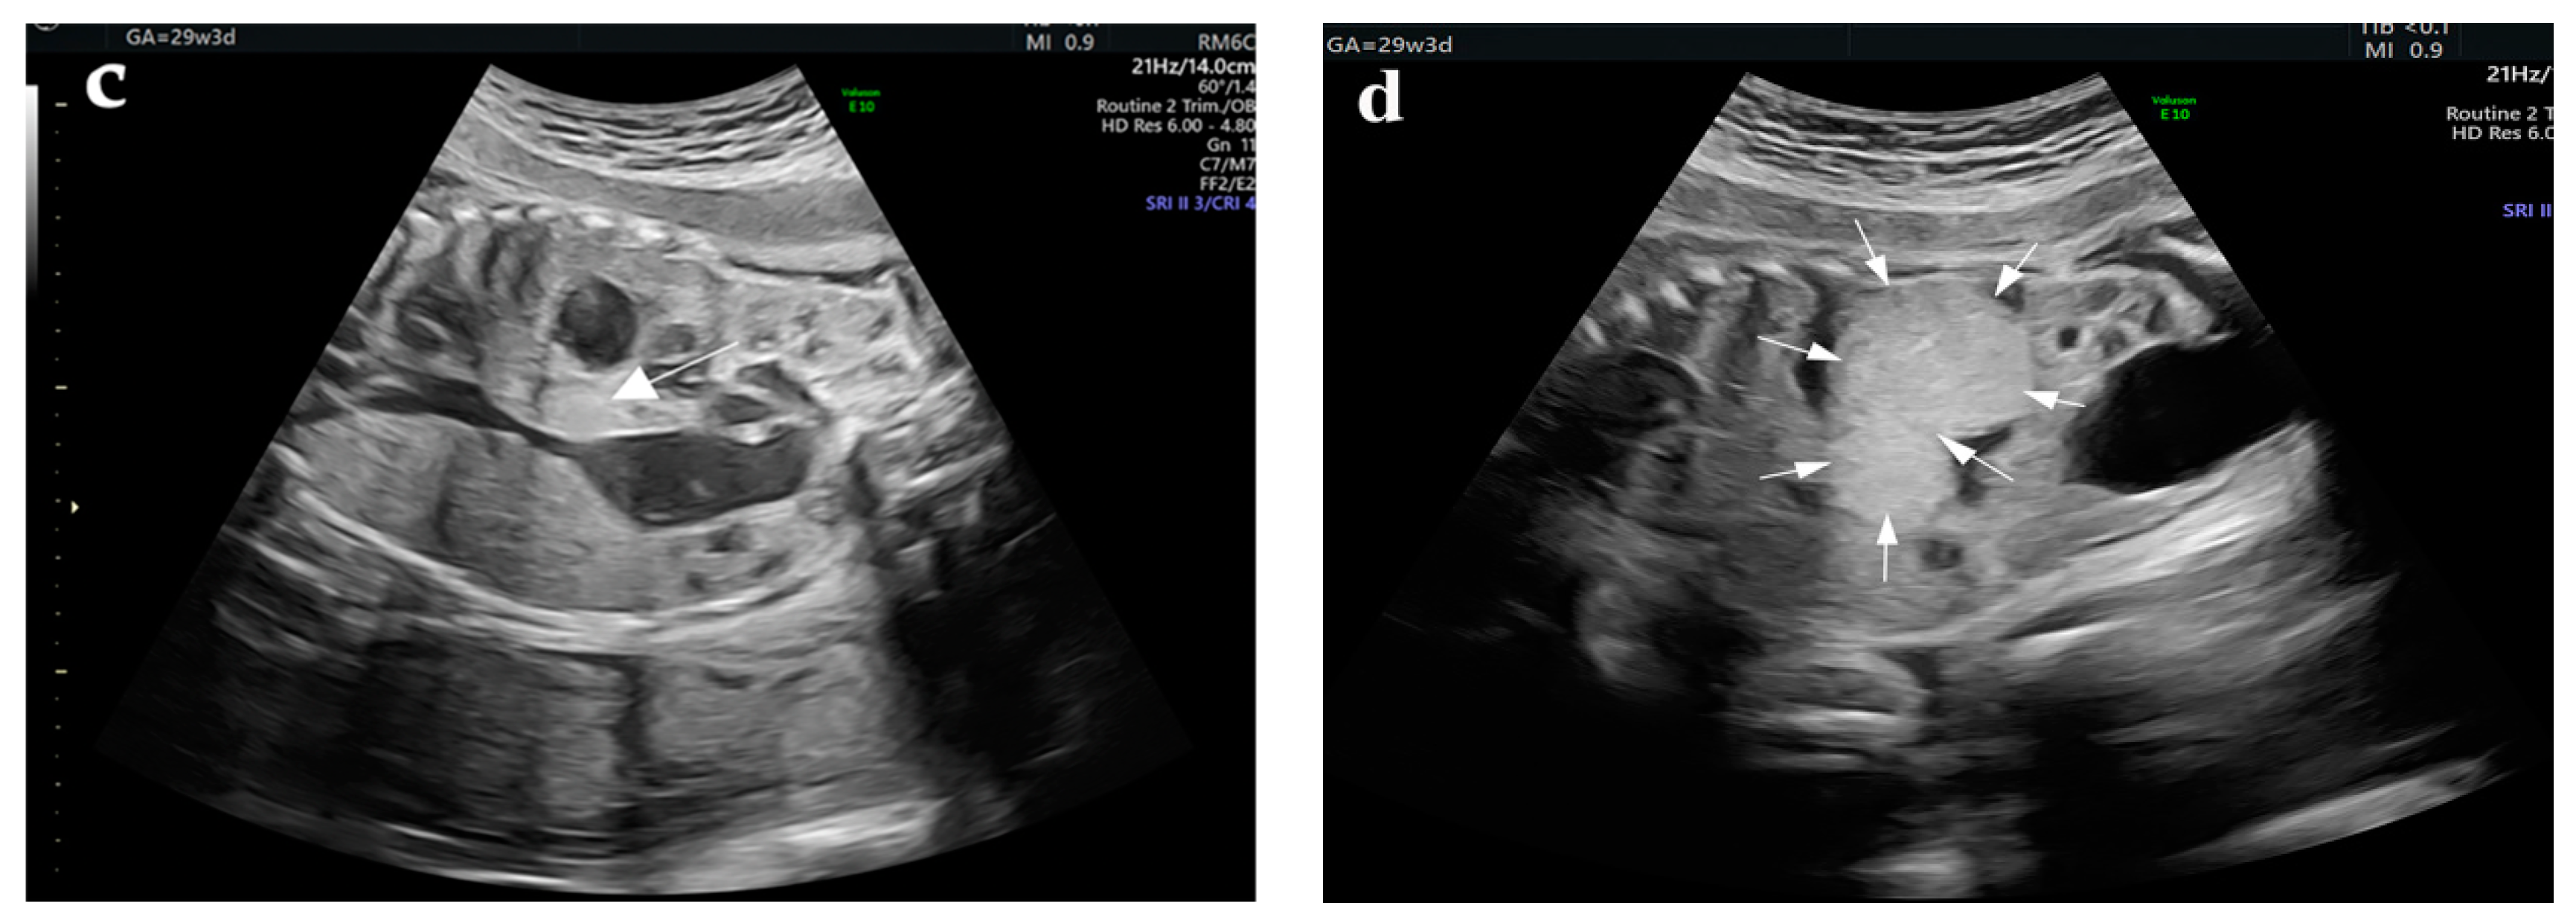

| Preoperative | Lung radiograph | 2nd day |

|

| CT of the thorax, abdomen, and pelvis | 6th day |

| |

| Postoperative | CT of abdomen and pelvis | Three weeks |

| CT of the brain, thorax, abdomen, and pelvis | Four weeks |

| Abdominal ultrasound | Five weeks |

| Abdominal ultrasound | Seven weeks |